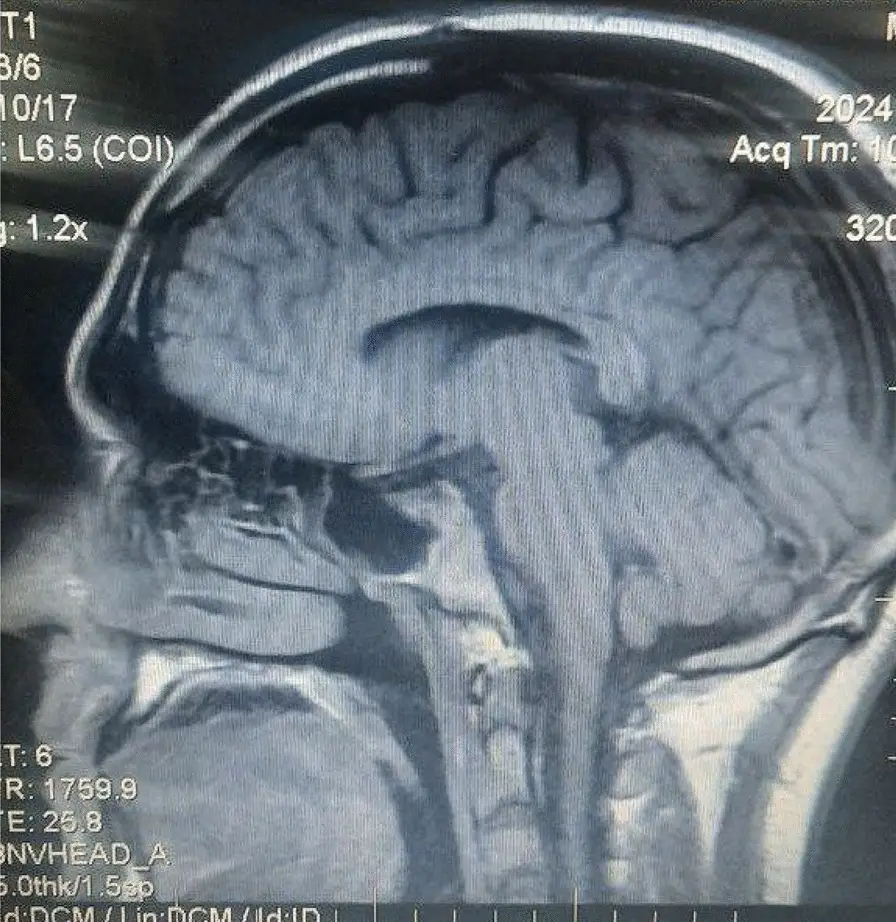

When the man finally sought medical help, scans of his head revealed that he had suffered a fracture at the base of his skull, with brain tissue and meninges (membranes protecting the brain and spine) herniating 'through the skull base fracture' and into the 'subarachnoid spaces in the right hemisphere'.

Put simply, parts of the man's brain was bulging through his right nostril.

The condition is known medically as encephalocele, which is often birth defect where portions of the brain tissue end up outside of the skull. However in this man's case, the condition was caused by head trauma instead of his skull not forming properly.